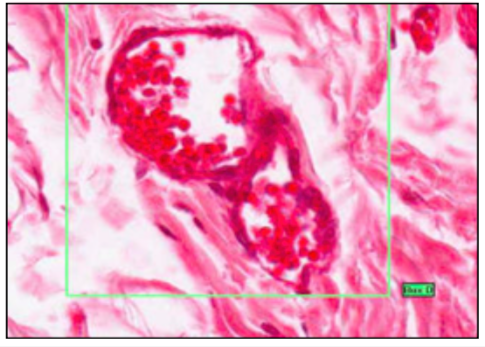

VENULES

- thin walled

- pericytes alongside them

- pericytes become continuous as vessel gets bigger

- in veins no pericytes, replaced by smooth muscle

- irregular outline

LYMPH VESSELS

- w/ pink staining blood plasma and valves

- small = like capillaries

- large = like veins

- walls = connective tissue with some muscle

- less pressure than venules

- sometimes lymphocytes

- transports antigens and activated lymphocytes from tissue to lymph nodes (and resident macrophage)

- drains excess fluid fro tissue (hydrostatic/oncotic pressure imbalance)

- no blood